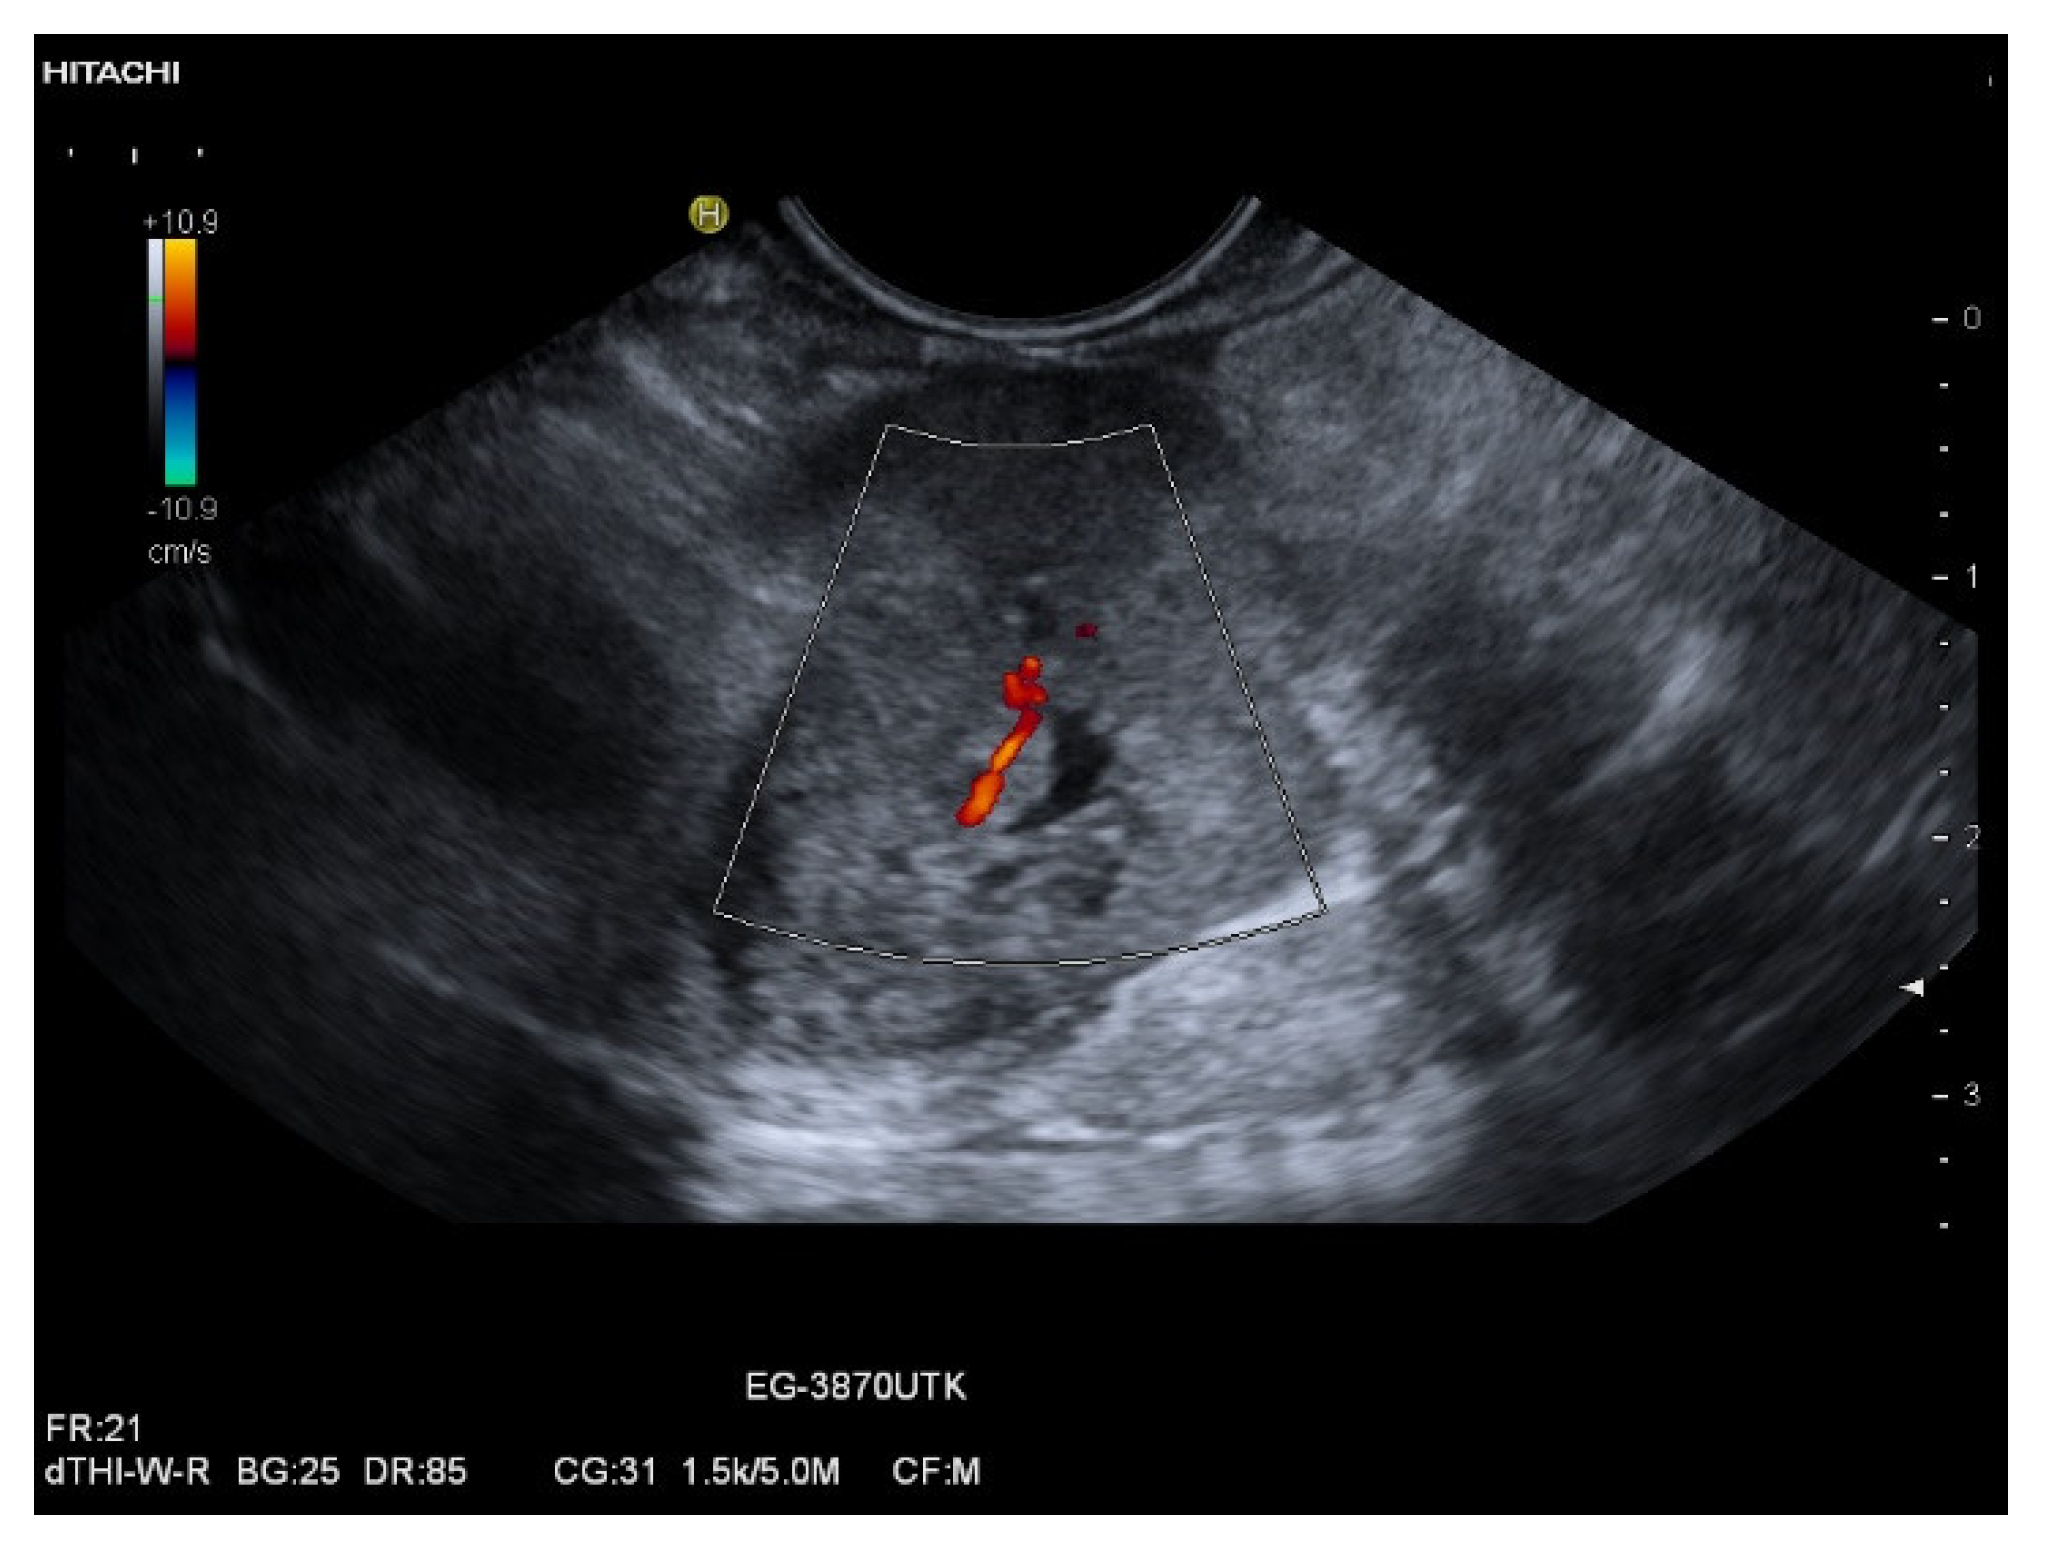

| Colour Doppler Imaging | RCC metastases are hypervascularized Most other pancreatic metastases are hypovascularized | No hypervascularization | Hypervascularized |

| RCC metastases [83] (n = 4) | Hyperenhancement, Early | Hyperenhancement | ||

| RCC metastases [61] (n = 3) | Hyperenhancement, homogeneous pattern | Slow washout | ||

| RCC metastasis [86] (n = 1) | Hyperenhancement, Inhomogeneous pattern | No washout | ||